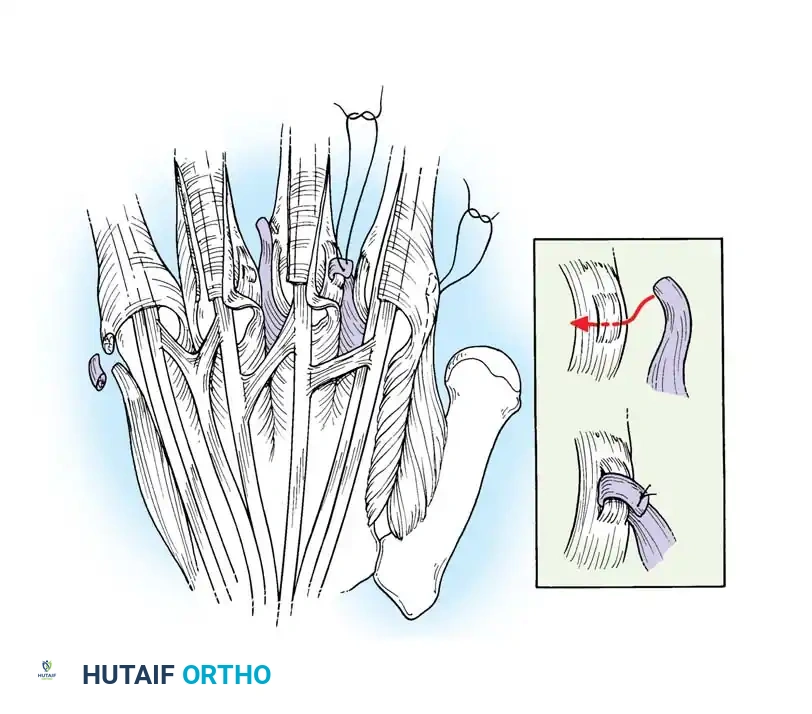

TECHNIQUE 70-1: Beckenbaugh

Incision and Exposure: Make a volar zigzag (Bruner) incision over the middle and proximal phalanges. Meticulously avoid damaging the digital neurovascular bundles, which may be displaced or adherent to the cruciate pulley system anterior to the hyperextended PIP joint.

Pulley Identification: Expose the cruciate pulleys by elevating the neurovascular bundles medially and laterally. Clearly identify and expose the A2 pulley.

Tendon Sheath Incision: Incise the central pulley system (C1/A3) centrally to expose the underlying flexor tendons.

Synovectomy: Retract the flexor digitorum profundus (FDP) tendon and release any adhesions. Expose the FDS tendon, release its adhesions, and perform a thorough flexor tenosynovectomy.

Tendon Preparation: Pull the FDS tendon distally and incise the decussation (Camper's chiasm), splitting the tendon into its two constituent slips. If necessary, extend the incision proximally and release adhesions at the A1 pulley level to allow adequate distal translocation of the tendon.

Splitting the FDS tendon into two slips at the level of the decussation. -

Slip Harvesting: Pull the divided FDS tendon distally and incise the ulnar slip proximally, leaving a 5-cm slip of tendon attached to its insertion on the ulnar side of the middle phalanx. Pull the slip firmly to ensure its insertion has not been compromised by erosive synovitis. (Note: In the little finger, both slips are often incised and used together because a single slip is usually too diminutive).

Pulley Fenestration: Puncture the A2 pulley 3 to 4 mm from its distal border using a scalpel or fine tenotomy scissors.

Tendon Routing: Pass a small curved hemostat through the hole distally into the sheath. Clamp the tip of the harvested FDS tendon slip and pull it proximally through the fenestration in the A2 pulley.

Tensioning and Suturing: Bring the slip of tendon distally, folding it back on itself. Adjust the tension so that the digit is held at exactly 5 to 10 degrees of flexion at the PIP joint. Suture the tendon to itself using nonabsorbable 4-0 braided sutures.

The completed FDS tenodesis, preventing PIP hyperextension while permitting active flexion.

- Closure: Repair the cruciate pulley if feasible. Close the skin over a small drain. Apply a sterile compressive dressing supported by a dorsal blocking splint to prevent hyperextension of the PIP joints.

Pitfall: Over-tensioning the tenodesis can result in a severe, iatrogenic PIP flexion contracture exceeding 30 degrees. Ensure the joint rests at no more than 10 degrees of flexion before final suture placement.